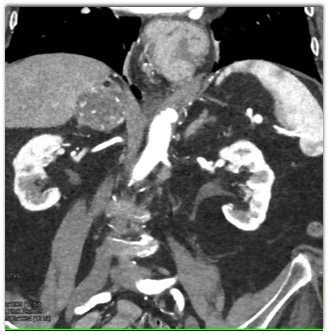

The best diagnosis in this patient with an incidental finding is

adrenal adenoma

adrenal pheochromocytoma

adrenal myelolipoma

adrenal carcinoma